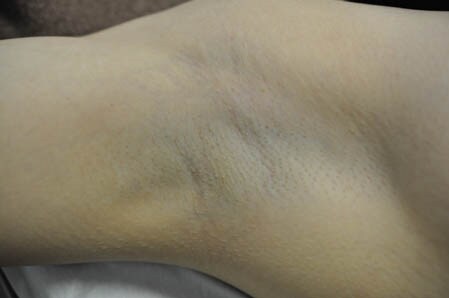

ワキの状態を比較して見てみましょう。 右ワキ

左ワキ

赤く内出血が見られますが

これはミラドライのヘッドの部分を

押し付けたことによるもの。

圧迫痕ですから強い出血とは

性質が全く異なりますので 1週間もかからずに

早い人だと数日で

元通りの状態に戻るでしょう。